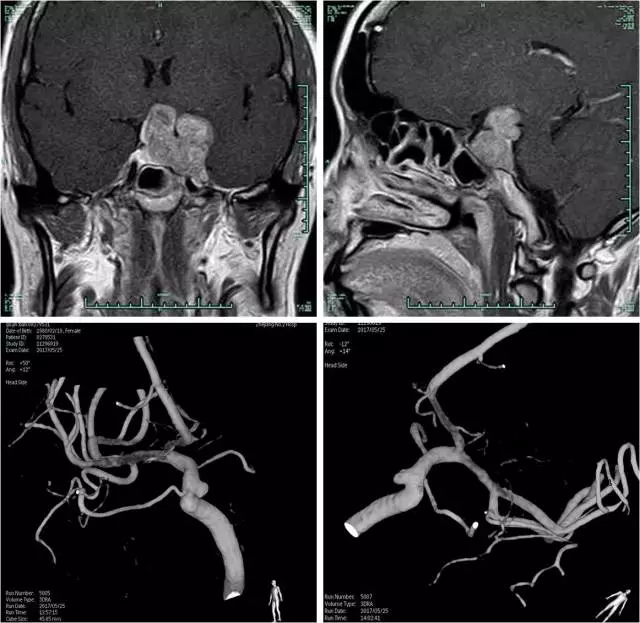

浙医二院的第二个病例是由闫伟副主任医师汇报的复发侵袭性垂体瘤合并双侧颈内动脉海绵窦段镜像动脉瘤。该患者治疗极具挑战性,因肿瘤侵犯海绵窦,并包绕后交通动脉;更为罕见的是肿瘤紧临双侧颈内动脉动脉瘤。该患者因肿瘤压迫造成视力减退,且为无功能性腺瘤,因此手术为首选方案。

但因前期已行支架辅助动脉瘤栓塞术,需服用抗血小板药物,这为手术进一步增加了难度。双方讨论后认为,患者需在停用抗血小板药物后尽早行手术治疗,而开颅手术可能较经鼻蝶手术安全性更高。